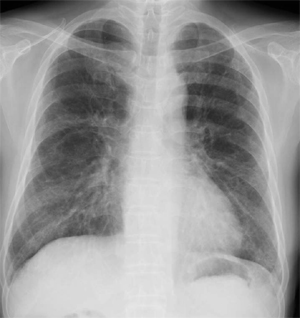

CXR PA

定期受診時(2010.05.10)Baseline

初診時(2010.05.19)

初診5日後 (2010.05.24)

(2010.06.11)背景肺に軽度の肺気腫+間質性肺炎像

(2010.07.18)縦隔リンパ節腫大